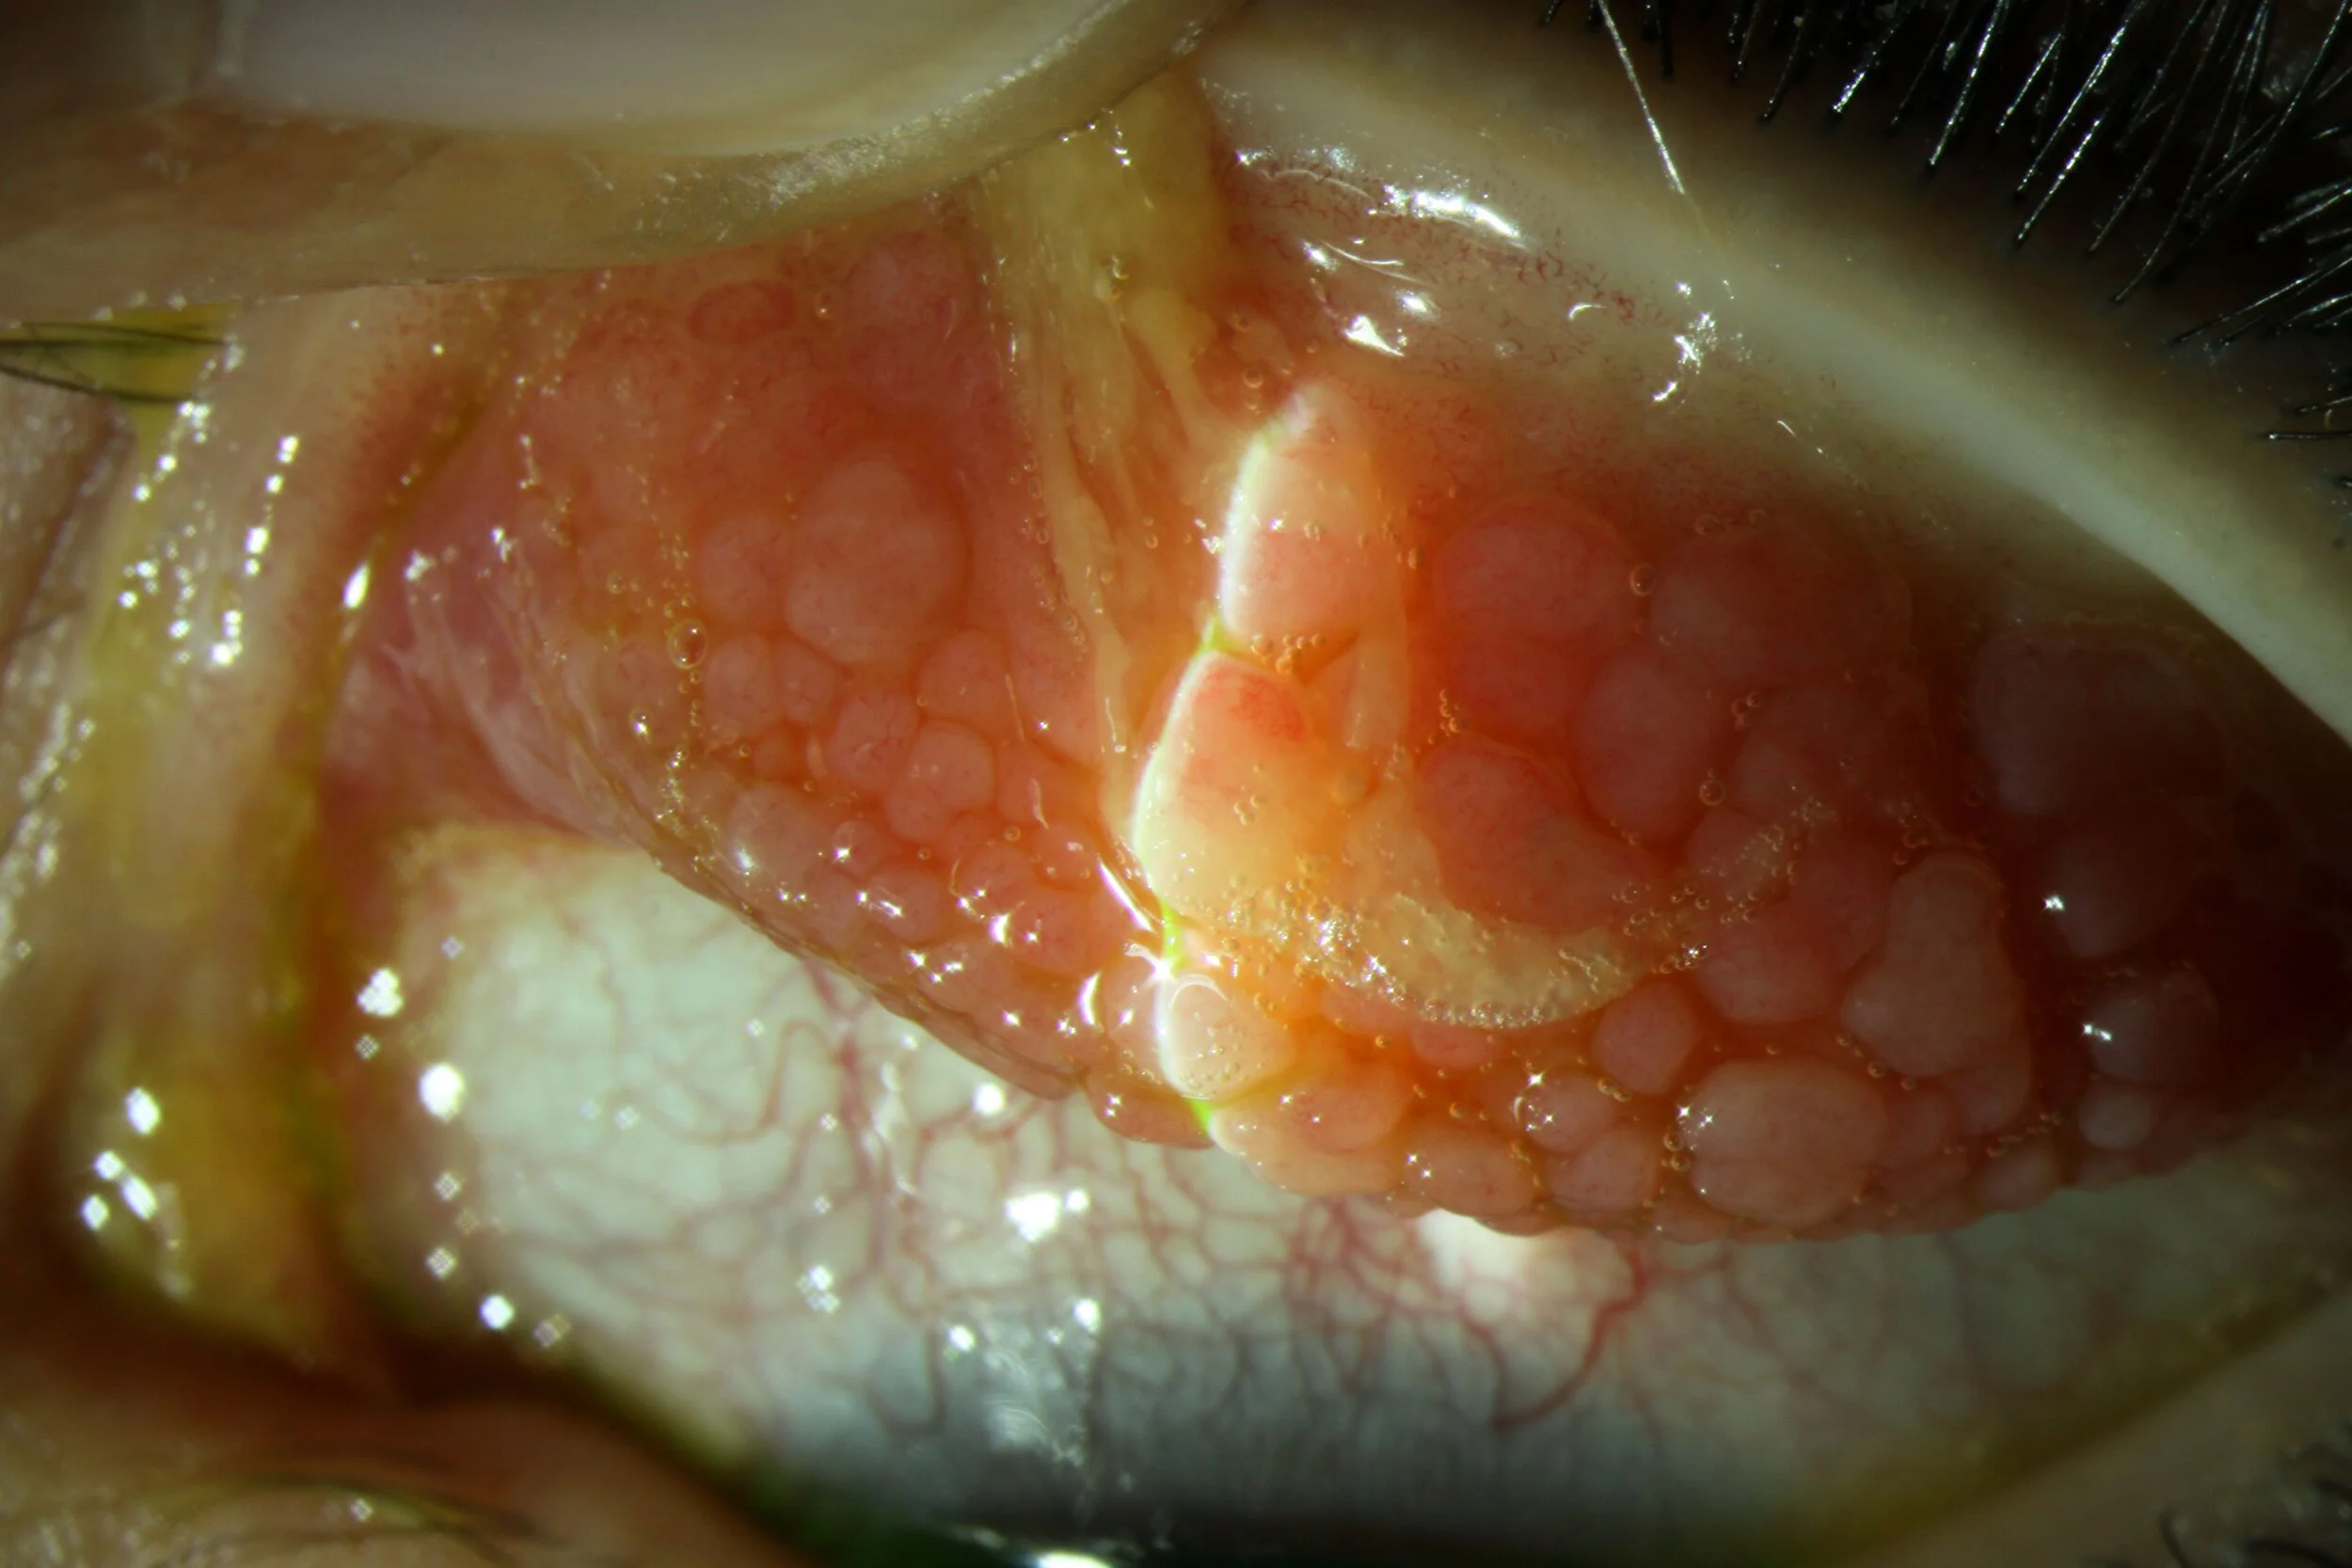

• Vernal Keratoconjunctivitis: Typically begins in childhood or adolescence and can be chronic and severe.

While allergic conjunctivitis is generally common and not sight-threatening, more severe forms, such as vernal and atopic keratoconjunctivitis, can lead to serious complications. It's essential to see an optometrist for an accurate diagnosis.